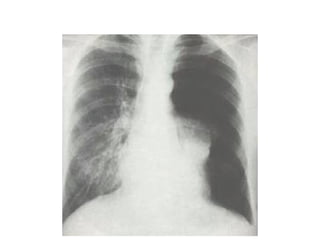

DERRAME MASIVO

• Desplazara al mediastino hacia el lado contrario, si esto no

ocurre se debe sospechar en malignidad debido a

obstruccion bronquial con atelectasia pulmonar, fijacion

del mediastino como ocurre con la infiltracion tumoral de

los ganglios linfaticos y atrapamiento del pulmon en el

mesotelioma maligno